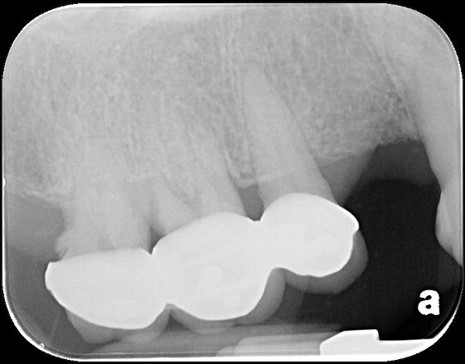

治療前,右上第一大臼齒疼痛

治療前,第一大臼齒根尖病變